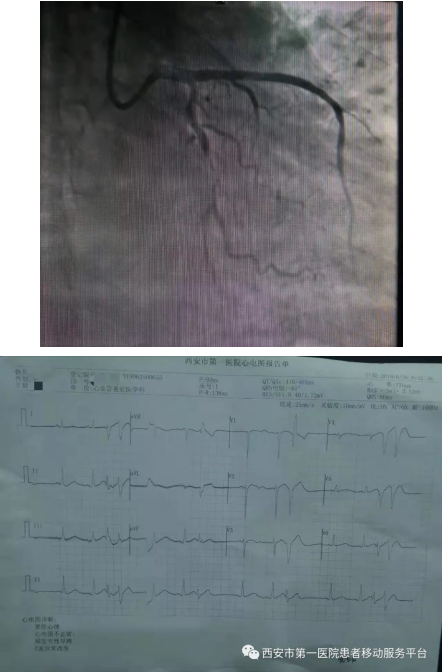

99次除颤抢救 4天3夜轮流守候 创造心内奇迹